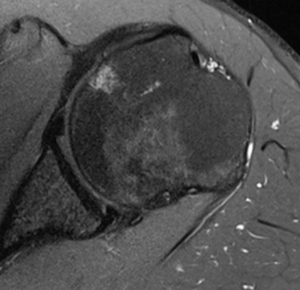

Magnetic Resonance Arthrogram (MRA)

Contrast enhancement during magnetic resonance arthrogram (MRA) is of great value and will increase the sensitivity of magnetic resonance imaging (MRI) in identifying a soft tissue injury (cartilage, rotator cuff, labral tears (Figure), a patulous capsule (Figure), reverse humeral avulsion of the glenohumeral ligaments (rHAGL, Figure), associated findings such as paralabral cysts) (Figure).